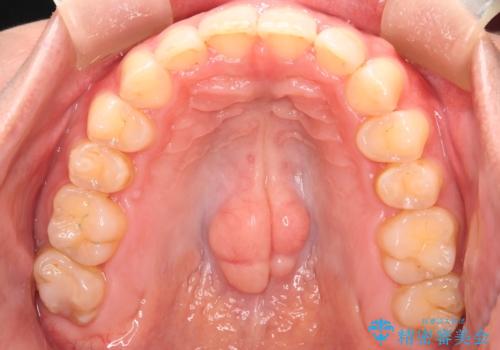

噛み合わせをよくするために、ワイヤー矯正とインビザライン矯正のどちらの期間も必要な箇所にゴム掛けを行いながら治療を行いました。

下の前歯のがたつき改善にはIPR(歯と歯の間を削る処置)を行いました。

ゴム掛けを頑張っていただいたので、噛みあわせも改善され綺麗な歯並びになりました。